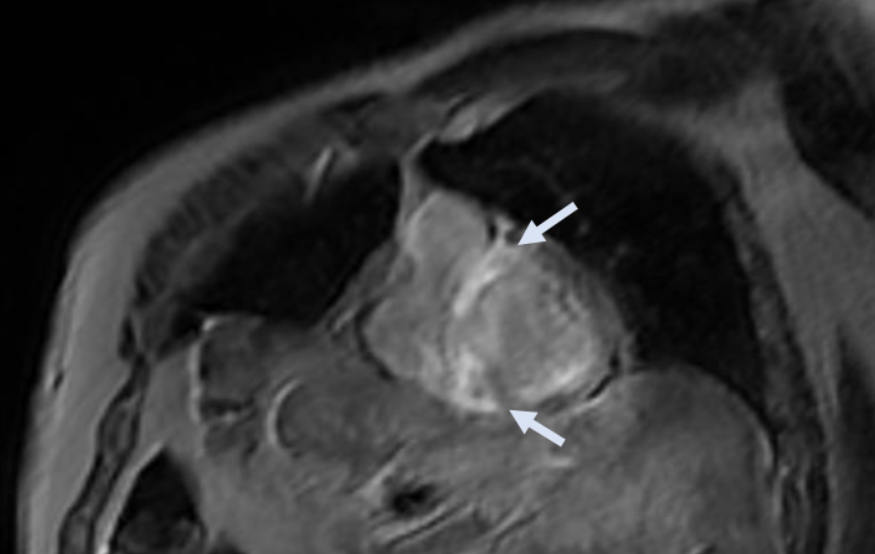

In view of the electro-anatomical discordance and the hypertrophic phenotype detected on the echocardiogram, CMR was performed. These results:

- Biventricular hypertrophy with preserved systolic function

- Infiltrative pattern with extensive areas of late gadolinium enhancement (LGE) predominantly intramyocardial at the level of the basal and middle septum, the basal postero-lateral wall, the papillary muscles and at the subepicardial-intramyocardial site of the anterior mid-basal wall and the inferior wall

- Presence of LGE also at the level of the atrial walls and the thickened interatrial septum

- Also presence of altered gadolinium kinetics, characterized by rapid uptake of the contrast agent into the myocardium at the expense of the blood contained in the cardiac chambers

CMR Images

- CMR: ventricular hypertrophy, altered gadolinium kinetics and diffuse finding of LGE with a non-ischemic pattern also involving the cardiac atria.